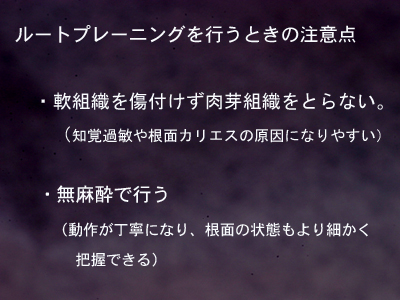

深いポケットを有する重度歯周病において、術後疼痛や冷水痛などの不快症状がなく良好な治癒に導きそれを再発させない秘訣は、ルートプレーニンングの開始時期にあります。『歯肉がブラッシングによって大きく変化したときに』『ポケット底から歯肉縁までの歯石を一気に』取り去って滑沢な根面に仕上げるのです。